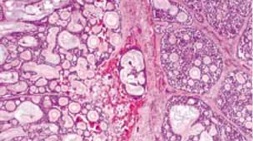

Pleomorphic adenoma (PA) is pseudoencapsulated and tends to be well-defined. It is characterized by epithelial and myoepithelial elements that form lumen and spindle structures that are mixed in with other mesenchymatous structures.[13][14]

© 2019 American Academy of Ophthalmology; Images obtained from AAO: https://eyewiki.aao.org/Pleomorphic_adenoma_(benign_mixed_tumor)_of_the_lacrimal_gland